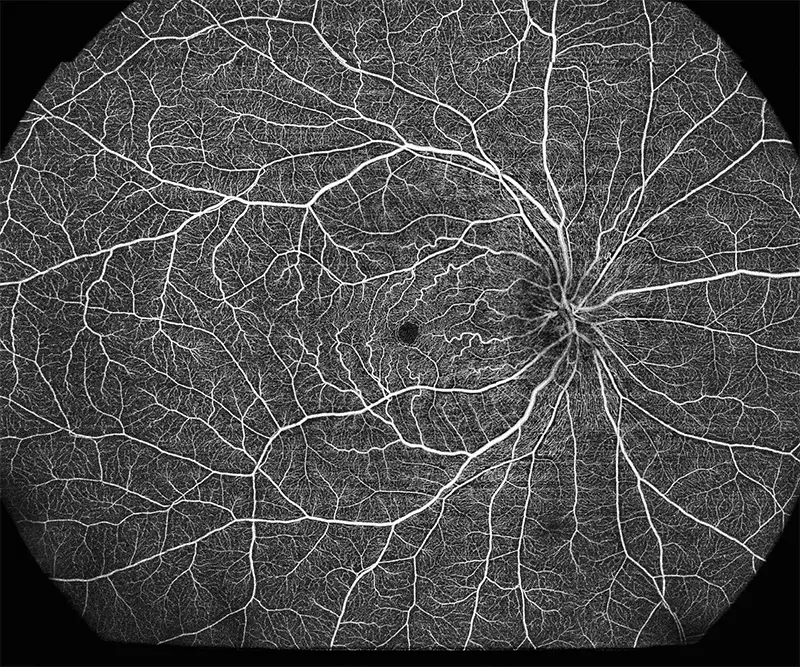

BMizar (BM-400K) es el OCT más potente de la industria con una fuente de barrido de 400 kHz. Su excepcional diseño óptico eleva la experiencia de la Angiografía OCT a un nivel sin precedentes. Con imágenes de alta definición de la retina, la coroides y el segmento anterior, cubre sin esfuerzo un área increíblemente grande en un solo escaneo (logrando un OCTA de 24 mm de ancho en solo 7-15 segundos).

Galería OCTs del TowardPi BMizar